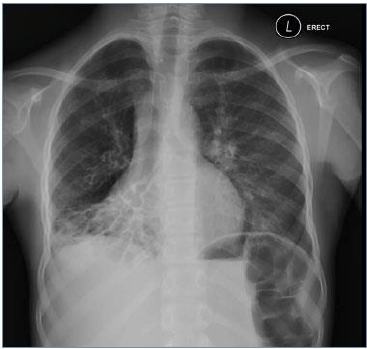

Considere a imagem radiológica abaixo:

http://www.residenciapediatrica.com.br/detalhes/285/leituras-de-radiografias-de-torax-em-criancas-suspeitas-de-possuir-tuberculose-pulmonar

A imagem acima, demonstra, perda de volume do lobo médio e inferior direito, com anéis de sinete típicos visíveis na região pulmonar afetada, altamente, sugestivo de: